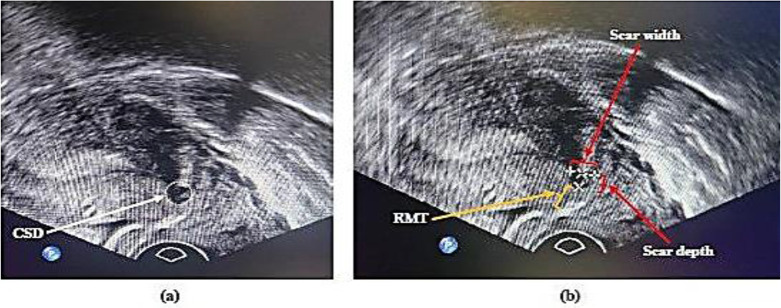

Materials and methods: We conducted a randomized double-blinded trial comparing double-layer locked and unlocked uterine closure techniques following cesarean section in primiparous women. The locked technique involved continuous suturing of the full myometrial thickness in the first layer, followed by back-and-forth needle maneuvering on both sides of the incision for the second layer. The unlocked method included running suturing of two-thirds of the myometrial thickness in the first layer, followed by suturing the upper half of the myometrial thickness in the second layer. Transvaginal ultrasonography was performed one year post-cesarean section, with RMT as the primary outcome and scar depth and width as secondary outcomes. Independent t-test and Chi-square test were utilized for statistical analysis.

Results: All 30 patients from the locked and 26 from the unlocked group in the follow-up were diagnosed with CSD (scar depth>2mm). The mean RMT for the unlocked and locked groups were 4.44±1.07mm and 4.12±0.48mm, respectively, showing no significant difference (p =0.14). There was also no significant difference in mean scar width between the locked and unlocked groups (3.68±1.44mm vs. 3.95±1.00mm, p =0.42). However, the mean scar depth was higher in the unlocked group (3.77±1.11 mm vs. 3.16±1.1mm, p =0.04).